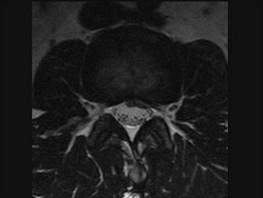

问题 腰椎间盘突出症(如图1)与腰椎管狭窄症(如图2)临床症状的主要不同点为 ( )

选项 A、双下肢无力情况 B、二便是否障碍 C、鞍区感觉改变情况 D、腰痛及下肢放射痛的程度 E、有否间歇性跛行

答案 E